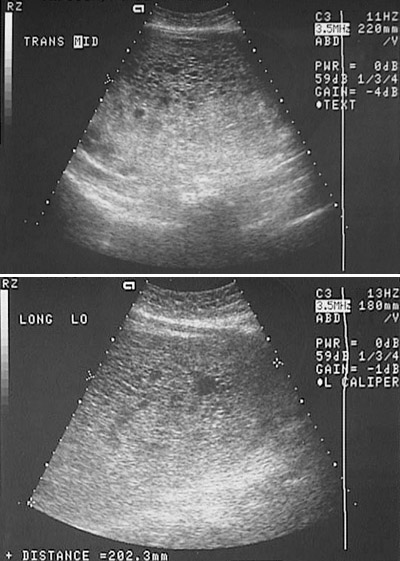

This ultrasound views of the pelvis demonstrates a large cystic mass in the uterine cavity which is consistent with a hydatidiform mole.